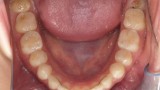

W pierwszym etapie diagnostycznym wykonano zdjęcia zewnątrz- i wewnątrzustne (ryc. 1-12).

Wykonano także modele diagnostyczne zaartykulowane w relacji centralnej (RC), którą zarejestrowano ze względu na zwiększone napięcie mięśniowe z wykorzystaniem deprogramatora Koisa (ryc. 13-15), oraz zdjęcie pantomograficzne (ryc. 16) i cefalometryczne. Analiza modeli w RC wykazała przesunięcie żuchwy w kierunku doprzednim w stosunku do pozycji maksymalnego zaguzkowania i przedwczesne kontakty funkcjonalne na zębach bocznych, co tłumaczyło obecność odprysków szkliwa na brzegach siecznych górnych zębów (szczególnie wyraźne na zębie 12) (ryc. 14, 17). Na modelach wykonano studium funkcjonalne mające na celu określenie, w jaki sposób można odtworzyć prawidłową funkcję, tzn. uzyskać prawidłowy nagryz pionowy i poziomy oraz prowadzenie przednie (ryc. 18-20).